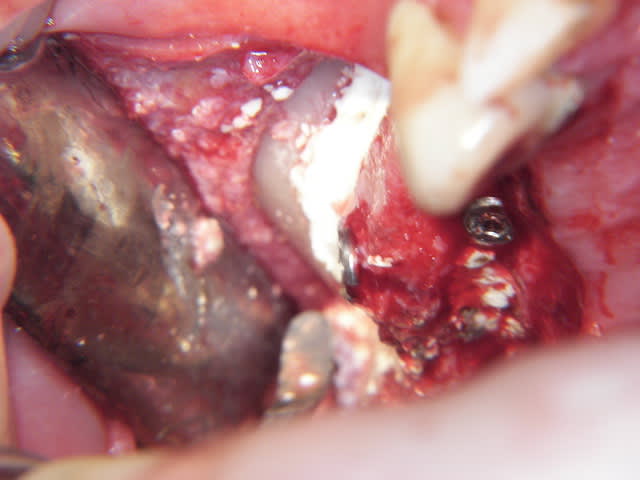

je viens de faire un sinus lift ce matin;

- 3 à 4 mm de hauteur sous sinusienne

- des cloisons de refend partout

- comblement avec du Vital Os

- un implant Axiom D4 L 10

comme je n'avais pas le temps de faire des photos la dernière fois et que j'en étais frustré, je me suis un peu lâcher aujourd'hui...

les premières photos, c'était ouverture par voie latérale

les suivantes;

- forage et transperçage de la crête sans aller trop loin...

- essayage pilier pour parallélisme

- forage à 3mm

- visualisation de la hauteur sous la membrane de Schneider

- utilisation d'un ostéotome diamètre 3.4 puis 3.8

(sous dimensionnement de diamètre par rapport à l'implant prévu :4mm)

- mise en place de l'implant

- séchage discret de la surface osseuse

- injection du Vital Os en palatin et partout autour de l'implant

- hé hé hé ... pas de membrane de recouvrement, le matériaux se suffit à lui même. d'où une petite économie substantielle pour ceux qui ont l'habitude de mettre systématiquement une membrane après un Caldwell-Luc.

- sutures...